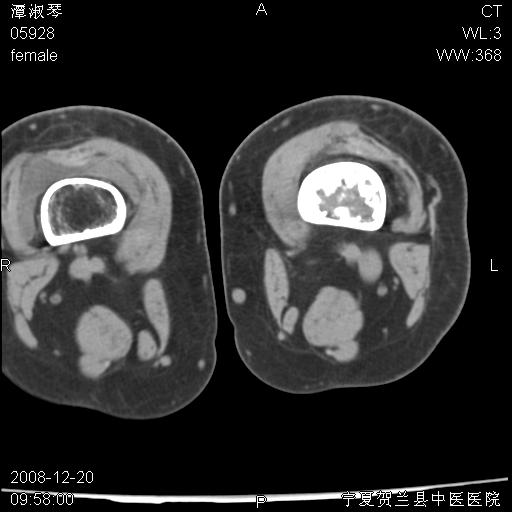

标题: CT17526:请各位看看是啥?

内生软骨瘤?骨梗死?

考虑内生软骨瘤可能性大

考虑-----骨梗死+退变

支持骨梗死,退行性骨关节病,膝关节积液.

考虑骨梗死可能性大

骨梗死可能性大

左股骨下段骨梗死。双膝退变。

左胫骨下端松质骨及髓腔内可见点片状高密度灶,骨皮质无明显膨胀及变薄。病变范围较长。支持骨梗死,退行性骨关节病,膝关节积液